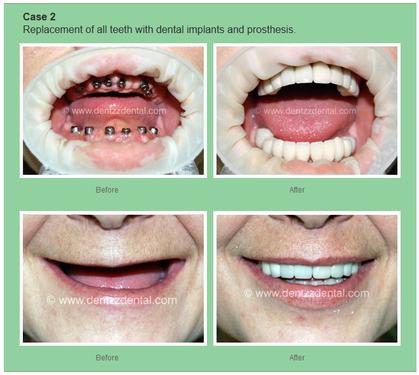

All on 4 Dental Implant Cost You should be prepared to spend an average of around $25,000 per dental arch for this solution. This could be as little as $12,000 or as much as $50,000. The higher marks will come from additional factors that go into the procedure such as bone grafting to strengthen the jawbone.